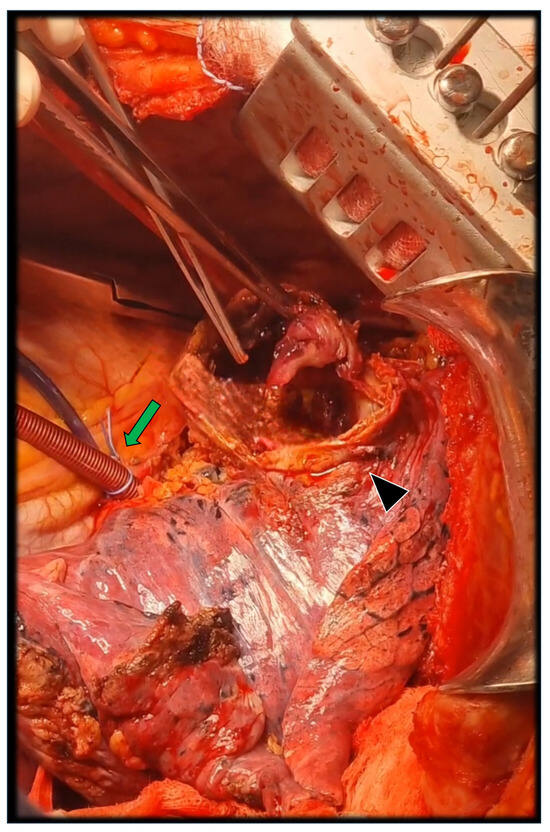

2. Case Report Description